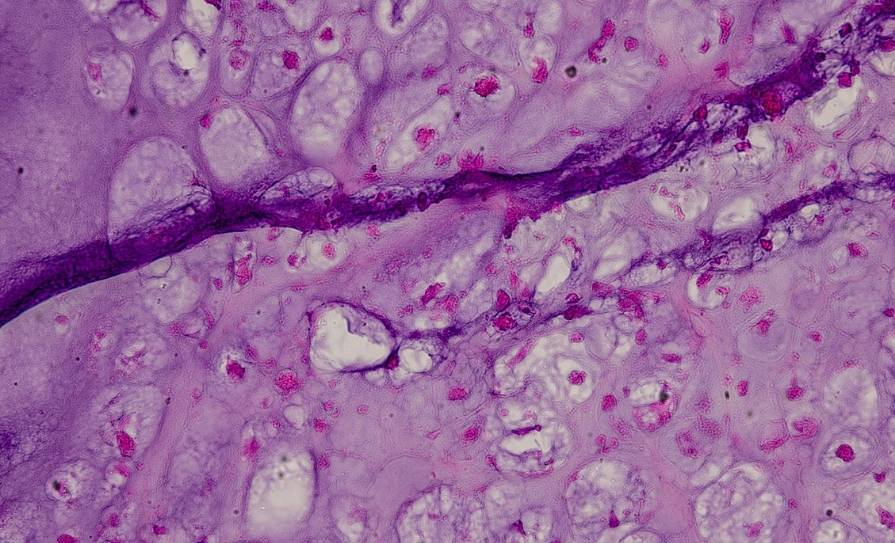

The pathogenesis of DKD involves a complex interplay of metabolic, haemodynamic, and inflammatory factors. Hyperglycaemia, hypertension, and dyslipidaemia are key contributors, leading to glomerular hyperfiltration, increased permeability of the glomerular basement membrane, and tubulointerstitial fibrosis.

Chronic inflammation and oxidative stress further exacerbate kidney damage, culminating in progressive renal function decline. The recognition and deeper understanding of this complicated milieu has led to advances in the application of novel agents to treat DKD.